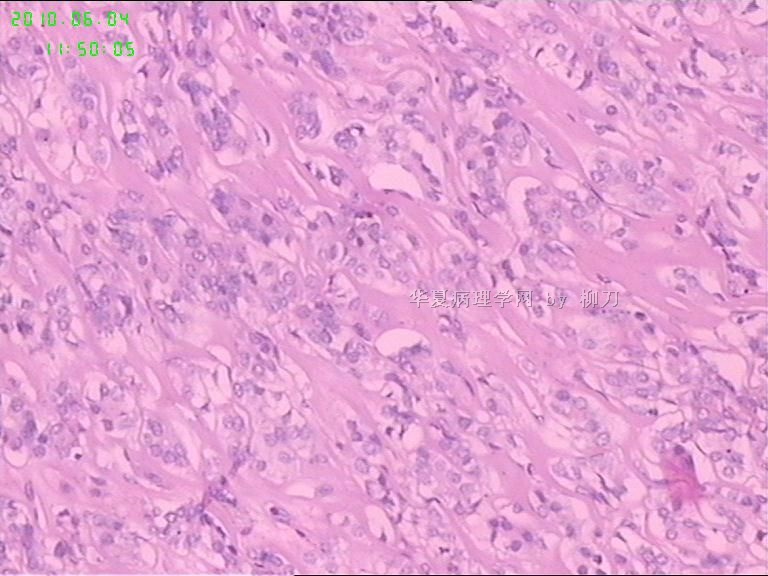

灰白结节2枚,其一2.5x1.8x1.5cm,包膜完整,内为褐色胶质,其二3x2.5x1.5cm包膜完整,切面灰白实性。附件镜下为后者。

可能楼主看到那些核的变化吧?但是没有其他支持的条件,还是应该是结甲。

就这几幅图似乎不够说明问题,细胞有一定的异型性,但是,最好能采到交界处的情况再判断。癌与非癌,最好能有组织结构与细胞异型性结合来看。

有些核透明,无其它特点,恶性证据是没有。